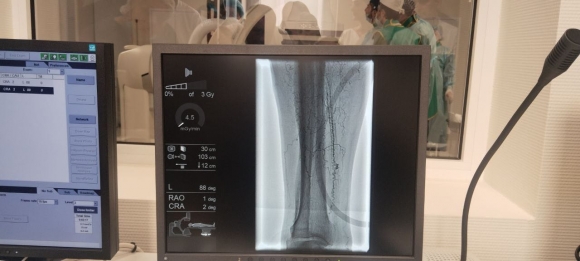

Основная задача командированных специалистов — запуск республиканского сосудистого центра на базе Республиканской больницы в г. Сухуме, проведение диагностических и лечебных мероприятий с использованием нового ангиографа. Аппарат был закуплен в этом году в рамках мероприятия программы социально-экономического развития Республики Абхазия.

— Первый пациент, которого прооперировали, — 80-летний мужчина. Он поступил с критической ишемией правой нижней конечности. Ситуация осложнялась коморбидностью пациента — у него также сахарный диабет, мультифокальный атеросклероз и критическая ишемия правой нижней конечности. В итоге удалось восстановить кровоток по двум артериям. Этого достаточно для того, чтобы восстановить кровоснабжение нижней конечности, и для того, чтобы у него зажили все те трофические нарушения, которые развились из-за ишемии, — сказал помощник генерального директора НМИЦ кардиологии им. Чазова Минздрава России Олег Милько.

— У второго пациента, 71 год, на сегодня была запланирована диагностическая коронароангиография, которая перешла в стентирование сердечных сосудов. У него диагностирована ишемическая болезнь сердца и нестабильная стенокардия. Коронарангиография показала 99% стеноз огибающей артерии. В результате проведенного стентирования кровоснабжение восстановлено, — отметил помощник генерального директора НМИЦ кардиологии им. Чазова Минздрава России Олег Милько.

Запуск ангиографа делает доступной плановую и экстренную медицинскую помощь пациентам с сердечно‑сосудистыми заболеваниями, в том числе – с инфарктами миокарда и ИБС, доступной. Этот аппарат позволяет обеспечить точную визуализацию повреждений сосудов и выполнить необходимые диагностические и интервенционные процедуры (ангиопластики, стентирования) на месте, что в том числе уменьшает необходимость транспортировки больных и повышает оперативность и эффективность кардиологической помощи в регионе.